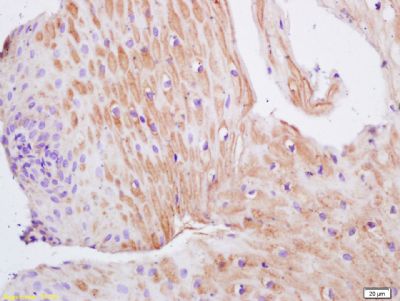

| 产品图片 | ![]() Sample: Lane1: Brain(Mouse) Lysate at 30 ug Lane2: Liver (Mouse) Lysate at 30 ug Primary: Anti-TIMP-1 (bs-0415R) at 1:200 dilution; Secondary: HRP conjugated Goat Anti-Rabbit IgG(bs-0295G-HRP) at 1: 3000 dilution; Predicted band size : 21kD Observed band size : 26kD ![]() Tissue/cell: human gastric carcinoma; 4% Paraformaldehyde-fixed and paraffin-embedded; Antigen retrieval: citrate buffer ( 0.01M, pH 6.0 ), Boiling bathing for 15min; Block endogenous peroxidase by 3% Hydrogen peroxide for 30min; Blocking buffer (normal goat serum,C-0005) at 37℃ for 20 min; Incubation: Anti-TIMP-1 Polyclonal Antibody, Unconjugated(bs-0415R) 1:200, overnight at 4°C, followed by conjugation to the secondary antibody(SP-0023) and DAB(C-0010) staining ![]() Tissue/cell: human colon carcinoma; 4% Paraformaldehyde-fixed and paraffin-embedded; Antigen retrieval: citrate buffer ( 0.01M, pH 6.0 ), Boiling bathing for 15min; Block endogenous peroxidase by 3% Hydrogen peroxide for 30min; Blocking buffer (normal goat serum,C-0005) at 37℃ for 20 min; Incubation: Anti-TIMP-1 Polyclonal Antibody, Unconjugated(bs-0415R) 1:200, overnight at 4°C, followed by conjugation to the secondary antibody(SP-0023) and DAB(C-0010) staining ![]() Tissue/cell: human colon carcinoma; 4% Paraformaldehyde-fixed and paraffin-embedded; Antigen retrieval: citrate buffer ( 0.01M, pH 6.0 ), Boiling bathing for 15min; Block endogenous peroxidase by 3% Hydrogen peroxide for 30min; Blocking buffer (normal goat serum,C-0005) at 37℃ for 20 min; Incubation: Anti-TIMP-1 Polyclonal Antibody, Unconjugated(bs-0415R) 1:200, overnight at 4°C, followed by conjugation to the secondary antibody(SP-0023) and DAB(C-0010) staining ![]() Tissue/cell: rabbit liver tissue; 4% Paraformaldehyde-fixed and paraffin-embedded; Antigen retrieval: citrate buffer ( 0.01M, pH 6.0 ), Boiling bathing for 15min; Block endogenous peroxidase by 3% Hydrogen peroxide for 30min; Blocking buffer (normal goat serum,C-0005) at 37℃ for 20 min; Incubation: Anti-TIMP-1 Polyclonal Antibody, Unconjugated(bs-0415R) 1:200, overnight at 4°C, followed by conjugation to the secondary antibody(SP-0023) and DAB(C-0010) staining |